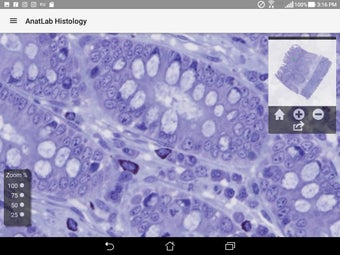

AnatLab Histology es una aplicación gratuita para Android desarrollada por Eolas Technologies Inc. que proporciona a los usuarios imágenes de diapositivas microscópicas de ultra alta resolución. Esta aplicación es una herramienta ideal para estudiantes, profesores, investigadores y el público en general. Con esta aplicación, pueden explorar el paisaje microscópico completo del cuerpo como si estuvieran mirando una colección de diapositivas reales en un microscopio físico. Tiene una función basada en la nube, la aplicación se puede acceder en cualquier dispositivo móvil Android, lo que la hace muy conveniente y accesible.

La aplicación ofrece una colección completa de imágenes de diapositivas microscópicas de histología que se pueden ver en ultra alta resolución. Las imágenes son de calidad excepcional y proporcionan una representación precisa del paisaje microscópico del cuerpo. La aplicación es fácil de usar y navegar, lo que permite a los usuarios explorar diferentes partes del cuerpo con facilidad.